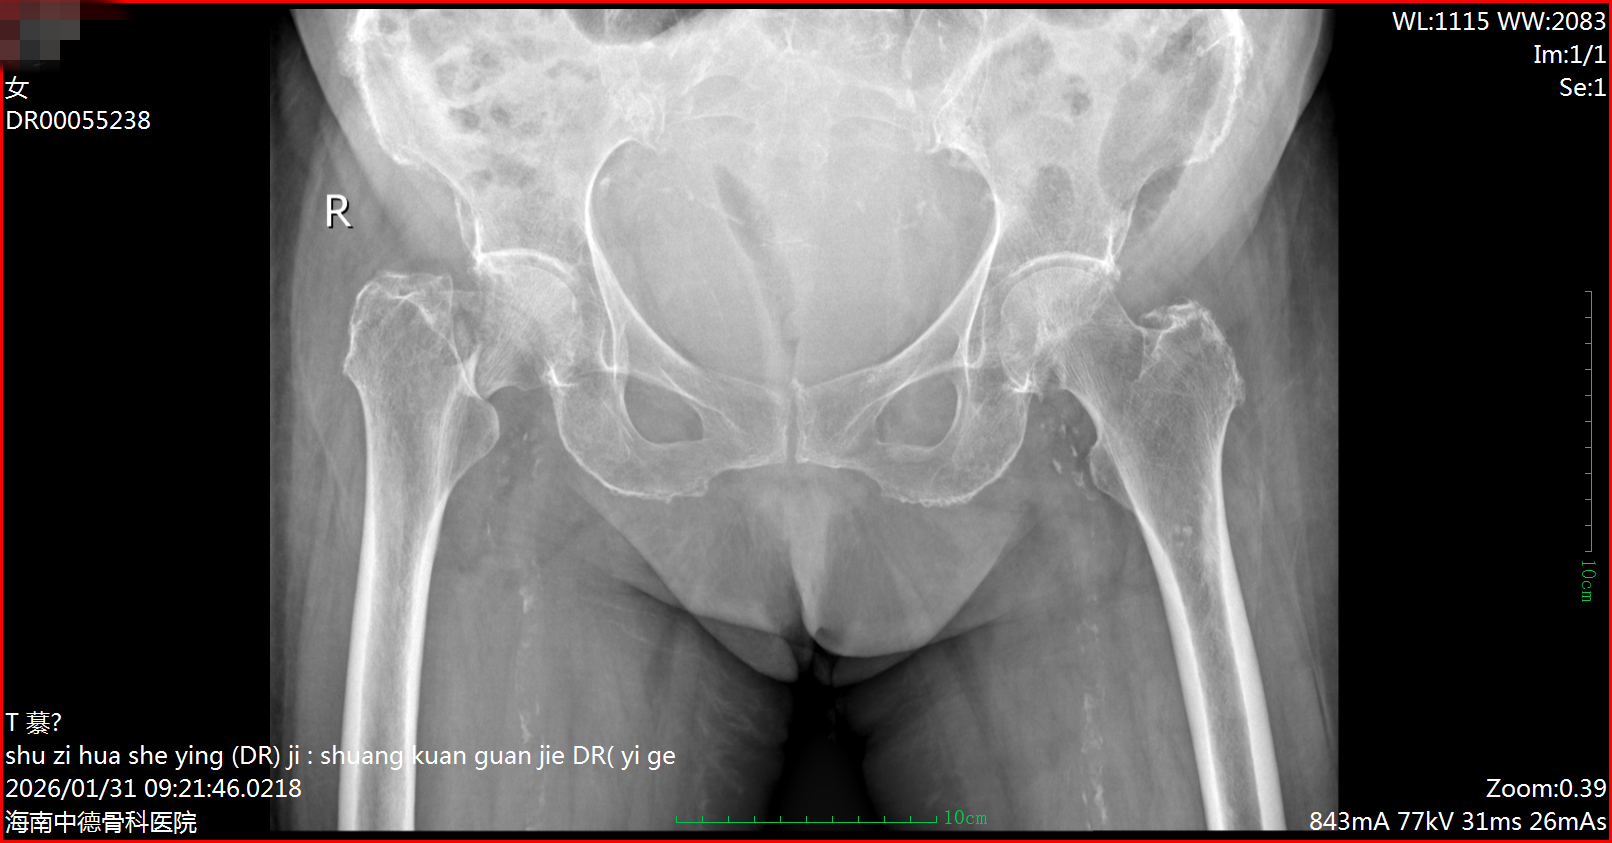

患者因外伤致右髋部骨折,此前因95岁超高龄及严重心脏病史(曾两次电击除颤),被外院评估为“手术禁忌”,建议保守治疗。为求手术机会,家属慕名转入我院关节外科。

术前DR片

入院后,挑战骤然升级。2月25日,患者因排便用力突发急性左心衰竭、心源性休克,病情急转直下,立即被转入ICU抢救。患者还同时患有冠心病、房颤、严重高血压、肝功能不全等多种高危疾病,手术风险呈几何级数攀升。